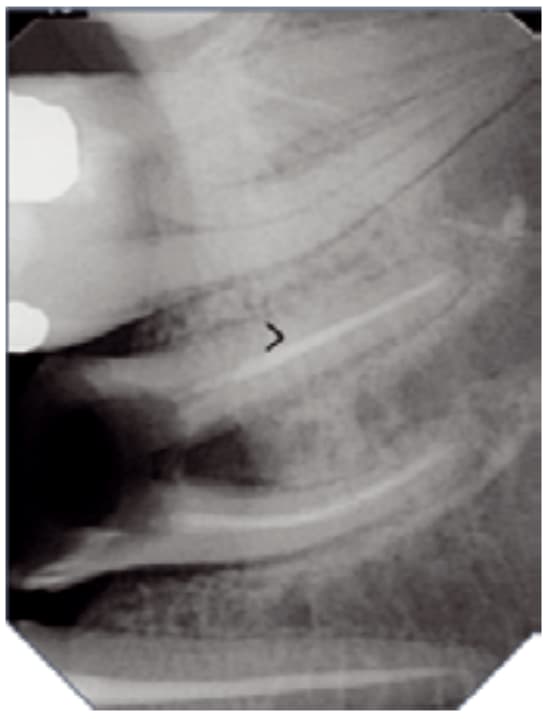

Wysoka rozdzielczość zapewnia dokładną i niezawodną diagnostykę. Technologia wielowarstwowa zapewnia obrazy o niskim poziomie szumów i z wyjątkową ostrością – w zaledwie kilka sekund.